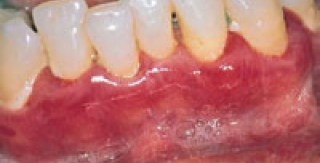

Tụt lợi là quá trình lộ bề mặt chân răng do sự di chuyển về phía chóp chân răng của lợi. Tụt lợi là điềm báo trước sự mất cement chân răng, lộ ngà, tăng cảm giác và giảm thẩm mỹ. Phương pháp điều trị tụt lợi tốt nhất là ghép nha chu chân răng.